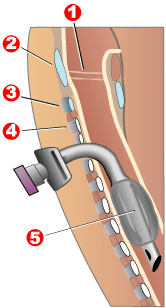

- Invasive Mechanical Ventilation – here a tracheostomy (insertion of a tube into the trachea from outside) is performed. It is only applied when the rest of the measures have failed (i.e., CPAP or NIV fails; deteriorating blood gases despite focused medical treatments) or conditions such as, clinical deterioration, sever respiratory acidosis or muscle fatigue. There are very high risks and complications of invasive mechanical ventilation and therefore it is only commenced in special cases and alway by a intensivist/specialist.

vocal cords:

1- Thyroid cartilage

2- Ring corpel

3- Tracheal cartilage

4- Balloon cuff